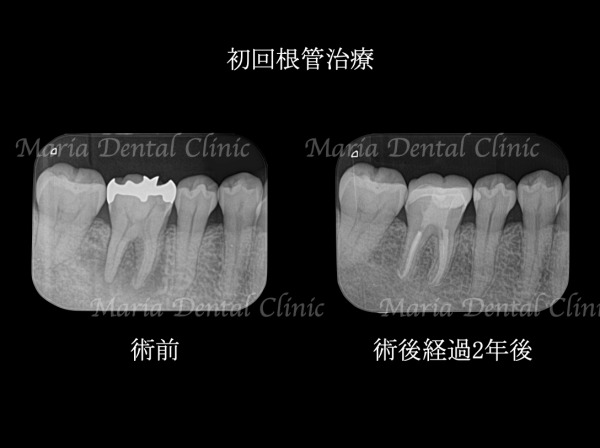

今回は初回根管治療終了後の3ヶ月で骨の再生が始まり、2年後には病変は完全に無くなるまでに回復しました(画像①)。